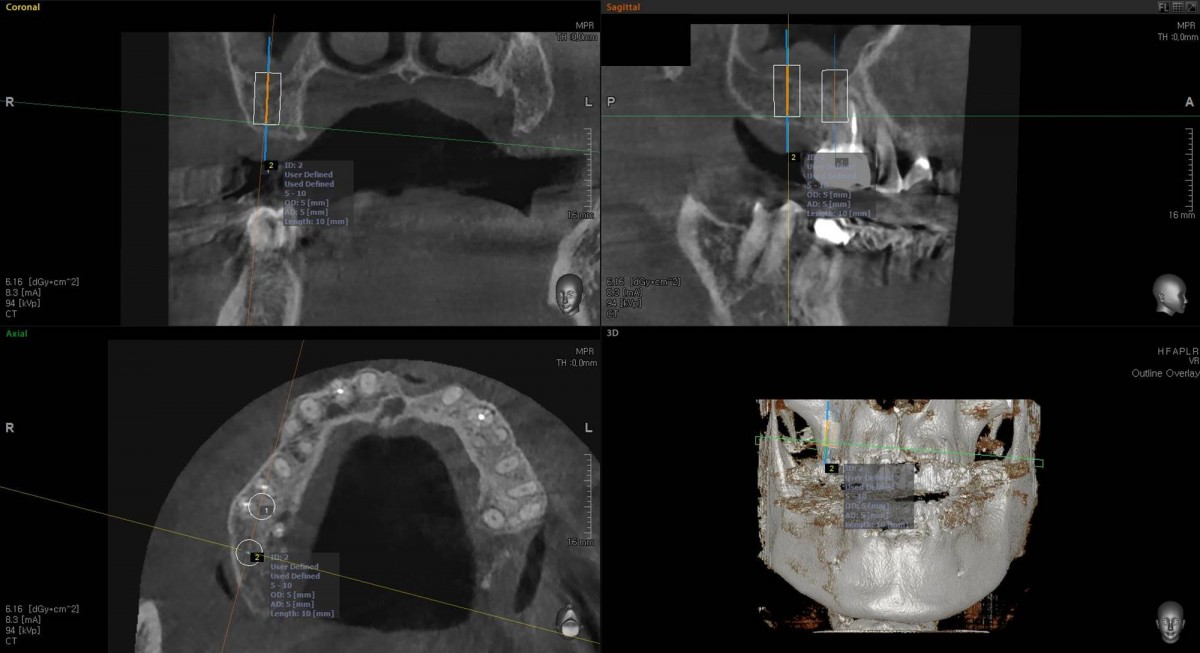

Socket Lift and Implant Placement in the right maxilla.

<GCacg> A 56-year-old male patient complained of pain in the right upper and lower jaws. And he wanted the upper first molar to be pulled out first.